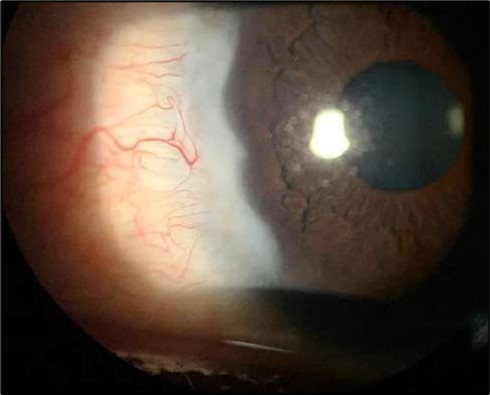

At six-months follow-up post-resection, the ulcer showed progressive epithelialization with no recurrence. Oral prednisolone was gradually tapered and stopped. The patient remains under regular ophthalmology follow-up with stable ocular findings Figure 6.

Figure 6.Six-month follow-up image showing a stable ocular surface, and absence of ulcer recurrence. The cornea appears clear centrally, with stromal scarring limited to the periphery.

Figure 7d.(6 months follow-up): OCT demonstrates complete structural restoration of the cornea with a smooth anterior contour, full re-epithelialization, and resolution of the ulcer defect. Mild residual stromal hyperreflectivity remains, consistent with fibrotic scarring. There is no evidence of epithelial breakdown or recurrence, indicative of a quiescent disease state